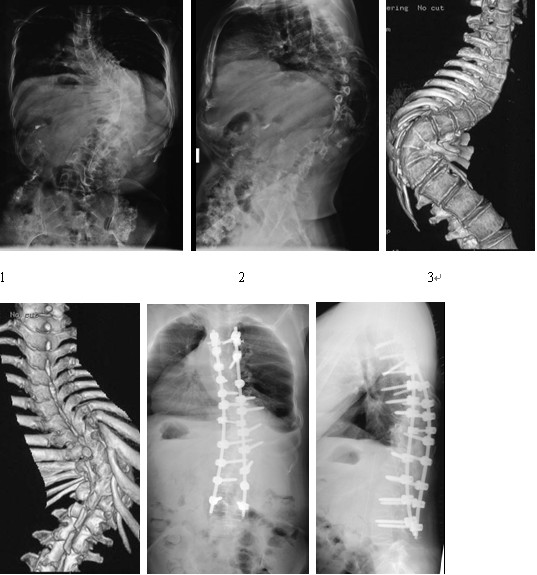

典型病例影像学资料见图1~6

所有患者均安全平稳度过围手术期,没有死亡或截瘫等严重并发症。平均手术时间270 min(215~380 min)。术中平均出血1560 ml(900~4800 ml)。在进行椎体去松质骨截骨时,平均切除2.1个椎体,平均固定融合10.6个节段(8~13个节段)。其中4例患者出现并发症:2 例出现一过性神经症状,未经特殊处理于1周左右恢复正常;1例脑脊液漏,经严格术中修补,术后引流痊愈;1例硬膜外血肿。术前冠状面Cobb角平均108°(92°~138°), 矫正至平均42º(32-51 º),平均矫正率为61%。矢状面Cobb角由术前平均82.0 º 矫正至28.7 º。所有患者获得平均31个月(24~48个月)的随访,末次随访时平均矫正丢失率为2%。在末次随访时所有患者在截骨部位均获得坚固的融合,没有发生假关节。所有内固定位置均良好,没有发现断钉断棒及内固定松动等并发症。